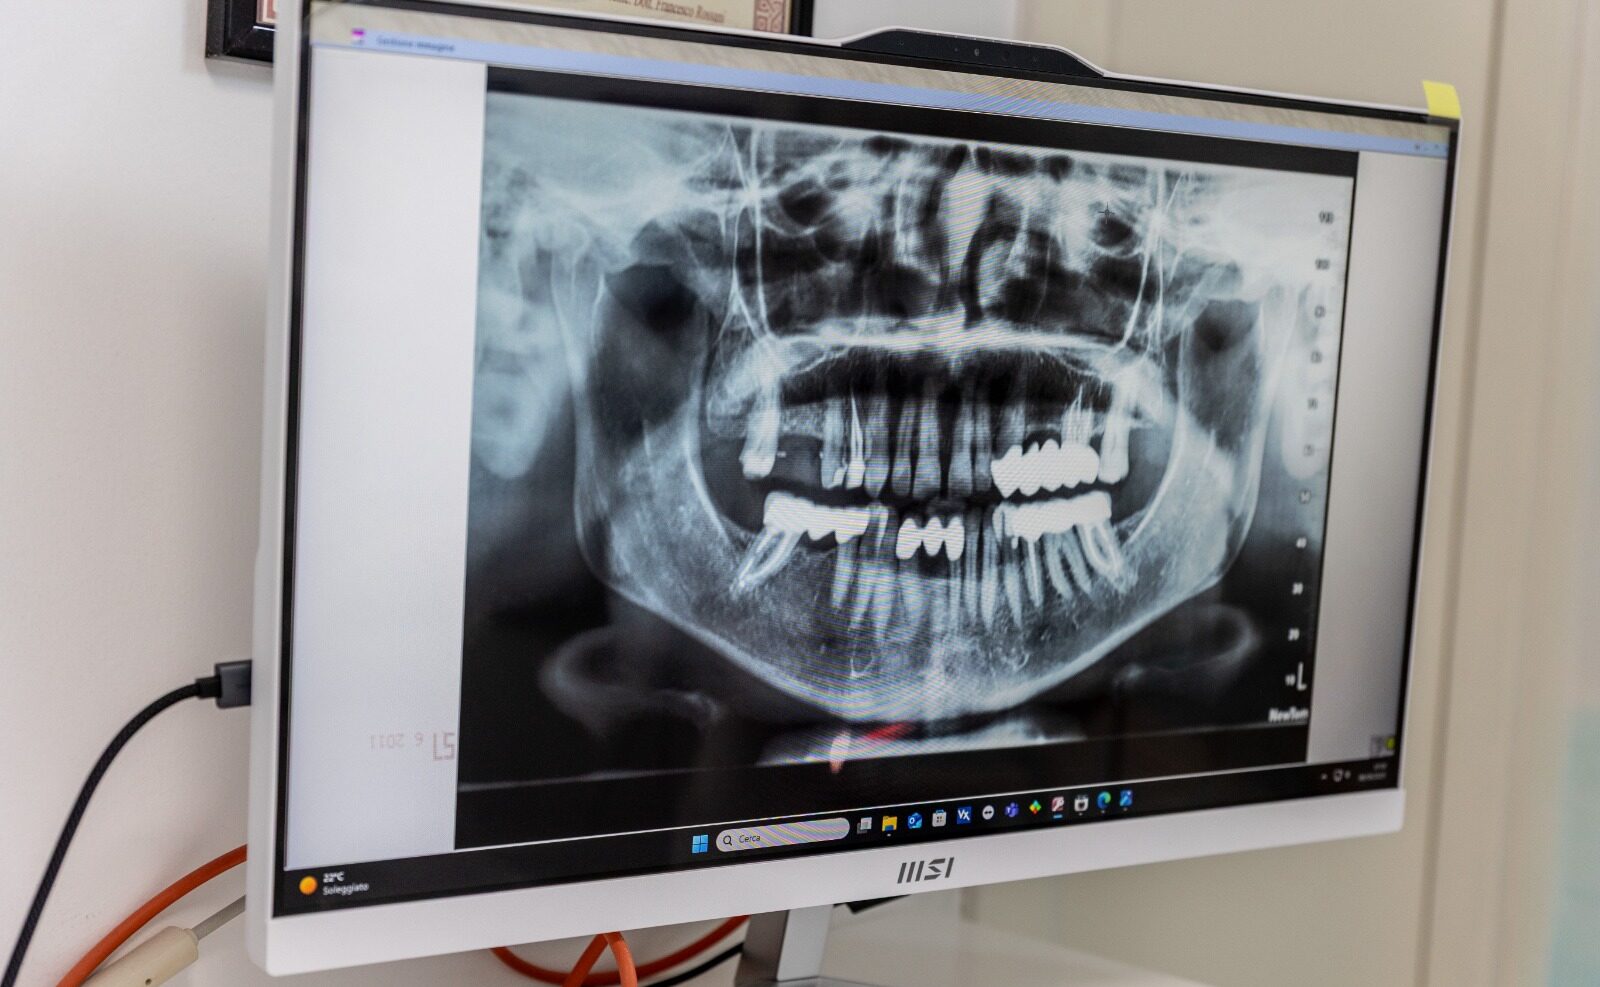

La gnatologia è la disciplina odontoiatrica che studia il corretto funzionamento del sistema masticatorio e i suoi rapporti con la postura e il benessere generale del corpo. Spesso non ce ne rendiamo conto, ma una scorretta occlusione dentale può essere strettamente collegata a disturbi come mal di testa, emicrania, cervicalgia, lombalgia, acufeni e dolori muscolari o articolari.

Muscoli masticatori, articolazione temporo-mandibolare (ATM), ossa mascellari e sistema nervoso lavorano in sinergia: un’alterazione di questo equilibrio può generare sintomi anche lontani dalla bocca. Per questo la gnatologia adotta una visione globale del paziente, valutando attentamente ogni singolo caso.